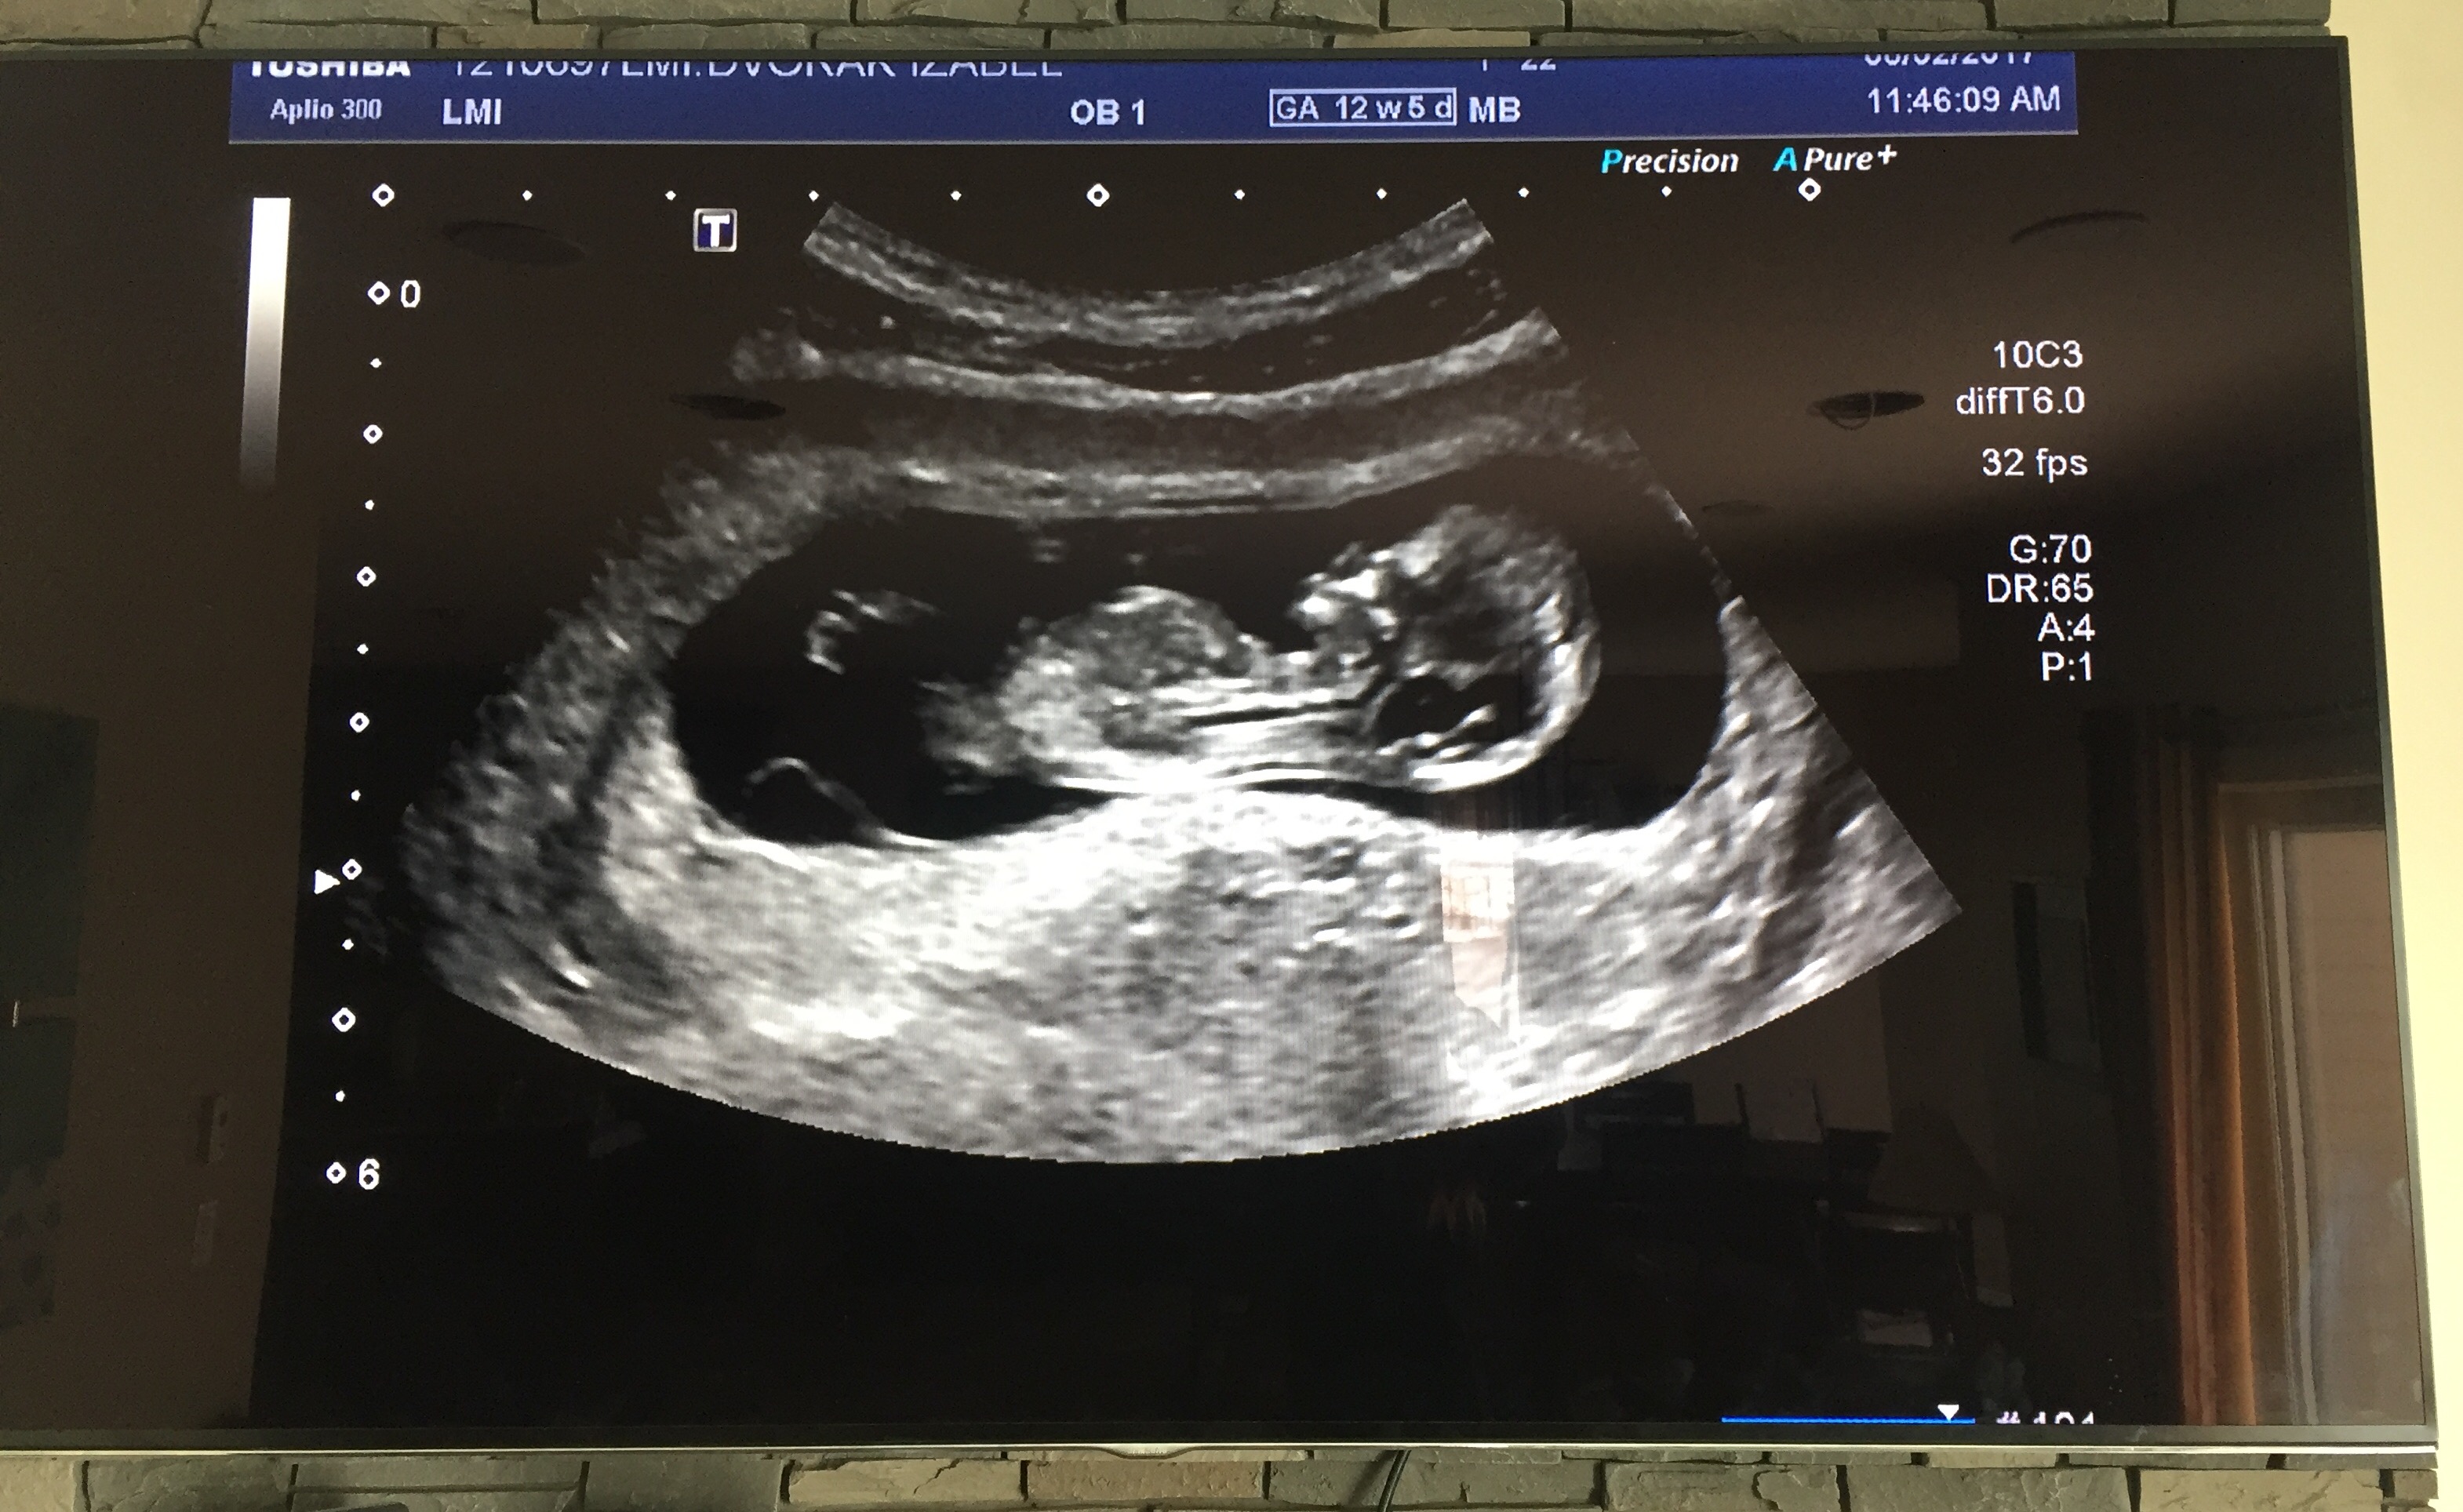

We thought I was 12w5d but I am measuring at 11w1d! does that look like the nub? If so any guesses? Also open to skull theory guesses too!![]()

I'm not sure there is a visible nub there, and 11+1 is too early, even though the baby looks more like a 12 weeker.

I'll give you a girly guess just for fun

Yay I was leaning to girly side too. Hopefully next week I get a better shot!